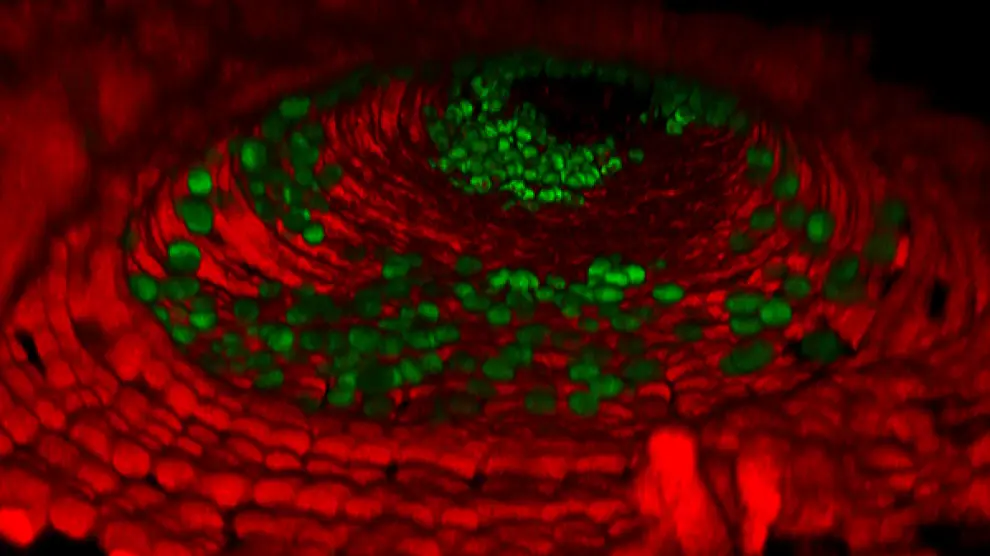

Científicos del 'Francis Crick Institute', financiados en parte por el Cancer Research de Reino Unido, han descubierto cómo un interruptor genético implicado en el empaquetamiento del ADN puede ser clave para la capacidad de una célula de cáncer de seguir creciendo. En concreto, encontraron que la producción de una proteína llamada H1.0 se apaga con frecuencia en muchos tipos de cáncer y que la reactivación de esta proteína detiene el crecimiento del tumor.

Mediante el estudio de las células cancerosas que carecen de H1.0, encontraron que el ADN se desenrolla en puntos clave, activando una serie de genes que detienen la célula en un estado 'inmaduro'. Esto permite que las células continúen con la división y la expansión del tumor.

Pero a medida que el tumor crece, H1.0 puede llegar a ser espontáneamente encendida en algunas células. Los investigadores vieron que esta nueva región del ADN actúa como el interruptor de control para la producción de H1.0. Con H1.0 volviendo a funcionar, se bloquean de nuevo los genes necesarios que necesita la célula para seguir creciendo, volviendo a una vida útil finita normal.